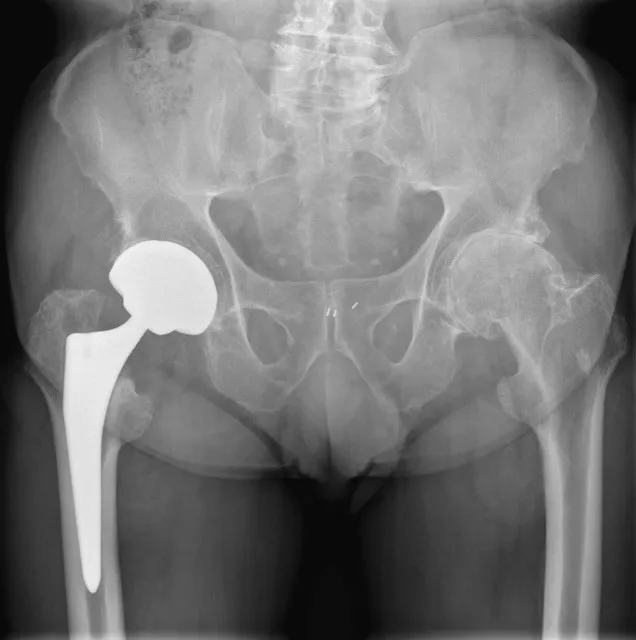

3. Heupprothese

Bij een verplaatste breuk in de hals van de heup waarbij de bloedvoorziening van de heupkop beschadigd is, wordt meestal een heupprothese geplaatst. De chirurg vervangt hierbij de beschadigde heupkop door een kunstkop met een metalen steel in het dijbeen. Afhankelijk van de patiënt wordt een halve heupprothese geplaatst (alleen de kop), of een totale heupprothese (kop en kom). Het plaatsen van een heupprothese zorgt voor een snellere mobilisatie na de ingreep zonder risico op afsterven van de heupkop (avasculaire necrose) met noodzaak tot heropereren. Deze optie is het meest geschikt voor oudere of minder mobiele patiënten die snel dienen te mobiliseren.